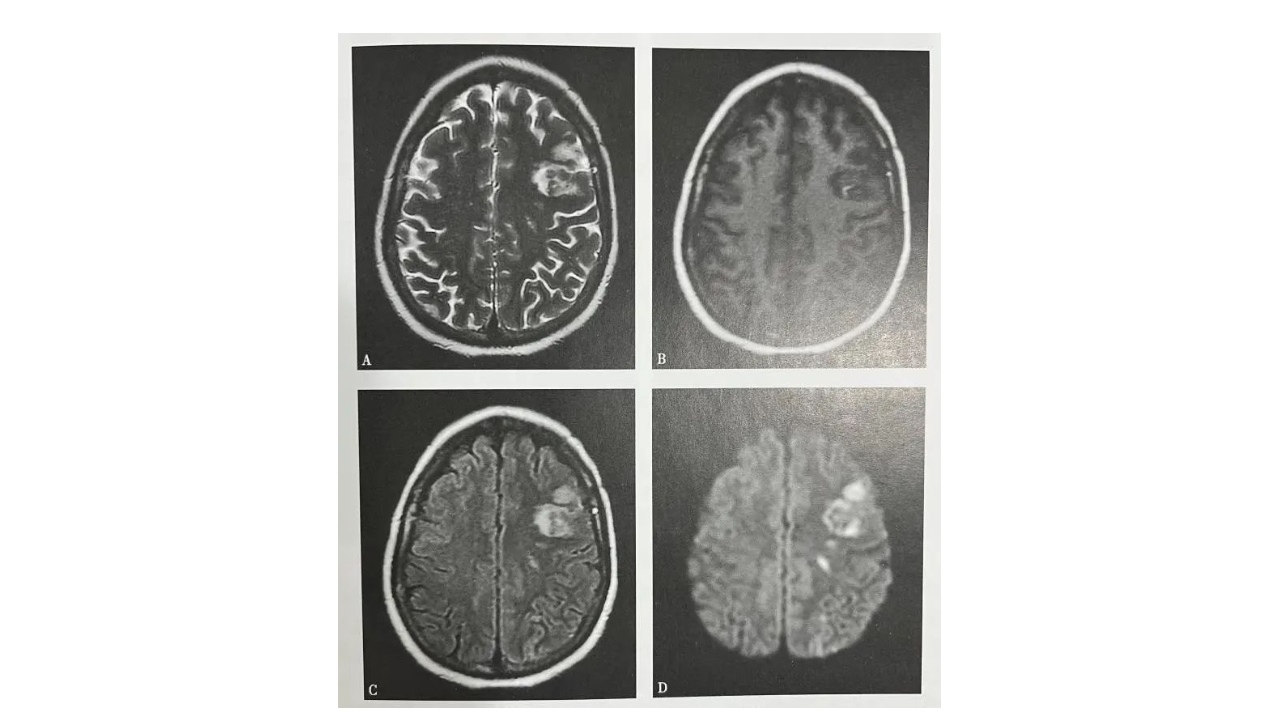

图1.图脑梗死(慢性期)

A~D(A.T2WI,B.T1WI,C.T2WI-FLAIR,D.DWI:右侧侧脑室体旁可见小片状长T1长T2信号灶,最大截面约12mmx10mm,边界尚清,FLAIR及DWI示病灶中心呈低信号灶,边缘呈稍高信号